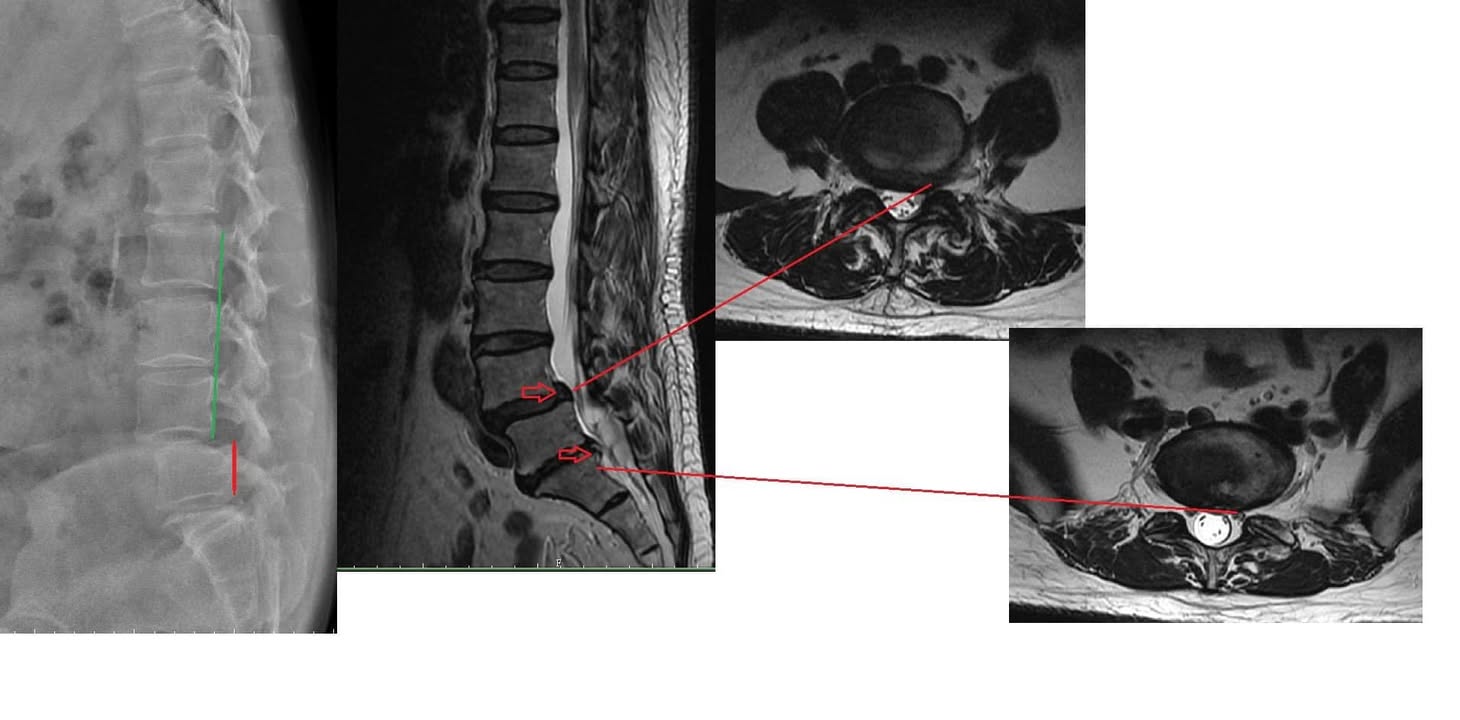

Cervical Spine Treatment Cases 腰椎治療案例 #今天來聊巨大骨刺為何可以吸收回去! #椎間盤突出需要多久才能吸收呢? #馬尾神經症候... 2020.09.08 #典型假性坐骨神經痛 #原來是梨狀肌症候群 #核磁共振排除椎間盤突出 #抽絲剝繭真相大... 2020.08.13 #嚴重椎管狹窄醫案 #感謝台北林大哥熱情見證 #從寸步難行到輕快漫步 #鍛鍊多裂肌的重... 2020.08.12 #椎間盤突出可以吸收回去嗎 #微針治療原理是什麼 #何時一定要接受神外開刀 #一張圖秒... 2020.08.11 #感謝花蓮鄉親林大姐熱情見證 #一分鐘認識椎管狹窄 #原本痛到無法走路打算開刀了 #脊... 2020.08.01 #感謝新莊區林先生熱情見證 #椎間盤突出跟纖維環裂隙的關係 #纖維環破裂突出可以不... 2020.07.28 #逆轉勝又一發case #原本疼痛一年多想說一定要手術治療了 #八週治療後症狀全部消失 #... 2020.07.25 #巨大椎間盤突出一定要開刀嗎 #除了開刀以外的選擇 #感謝台北市吳先生熱情見證 2020.07.24 #腰椎滑脫的疼痛心酸誰人知啊 #一分鐘瞭解腰椎滑脫 #哪一種情況需要積極開刀 #要如何... 2020.07.21 #巨大椎間盤脫垂一定要開刀嗎? #感謝新店林先生熱情見證受訪 #西醫手術有那些選擇... 2020.07.02 #纖維環裂隙AnnularFssures #MRI看起來不嚴重卻嚴重困擾患者 #感謝桃園市蕭先生熱情見... 2020.06.19 #骨刺有可能吸收回去嗎?? #疼痛超過六年的特殊案例探討 #MRI核磁共振前後對比 #感謝... 2020.06.14 #坐骨神經痛一定要開刀嗎 #突出的骨刺真的可以自己吸收嗎 #最新英國醫學期刊BMJ的看... 2020.05.30 #骨刺跟突出髓核有可能吸收回去嗎?? #特殊案例探討 #核磁共振一年後對比 2020.05.29 #從醫以來第一次碰到薦椎Tarlov cyst囊腫#左邊紅色圈圈是個案,右邊是國外案例#腰... 2020.05.23 ← 上一頁 10 11 12 13 14 下一頁 →